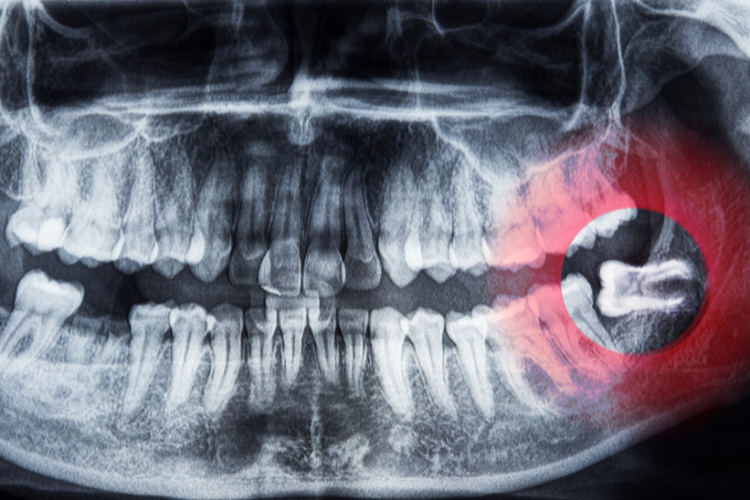

An impacted tooth is a tooth that does not properly erupt. After the wisdom teeth, the most commonly impacted teeth are the canine teeth. The canine teeth are incredibly important, helping you to chew properly and framing your smile to give you a more aesthetic appearance. Impacted canine teeth can also cause damage to the adjacent teeth, leading to tooth loss or the development of other problems around the tooth, such as cysts or tumors. One of the treatments our oral surgeon may recommend to treat an impacted canine tooth is exposure and bonding.

Canine exposure and bonding involves uncovering the impacted tooth and bonding an orthodontic attachment to it. This attachment is connected to a small chain, usually made of gold, and a rubber band. The chain and band work to apply gentle traction and pressure to help the tooth erupt and move into the correct position in the mouth. This is a slow, careful process and may take up to a full year to complete.